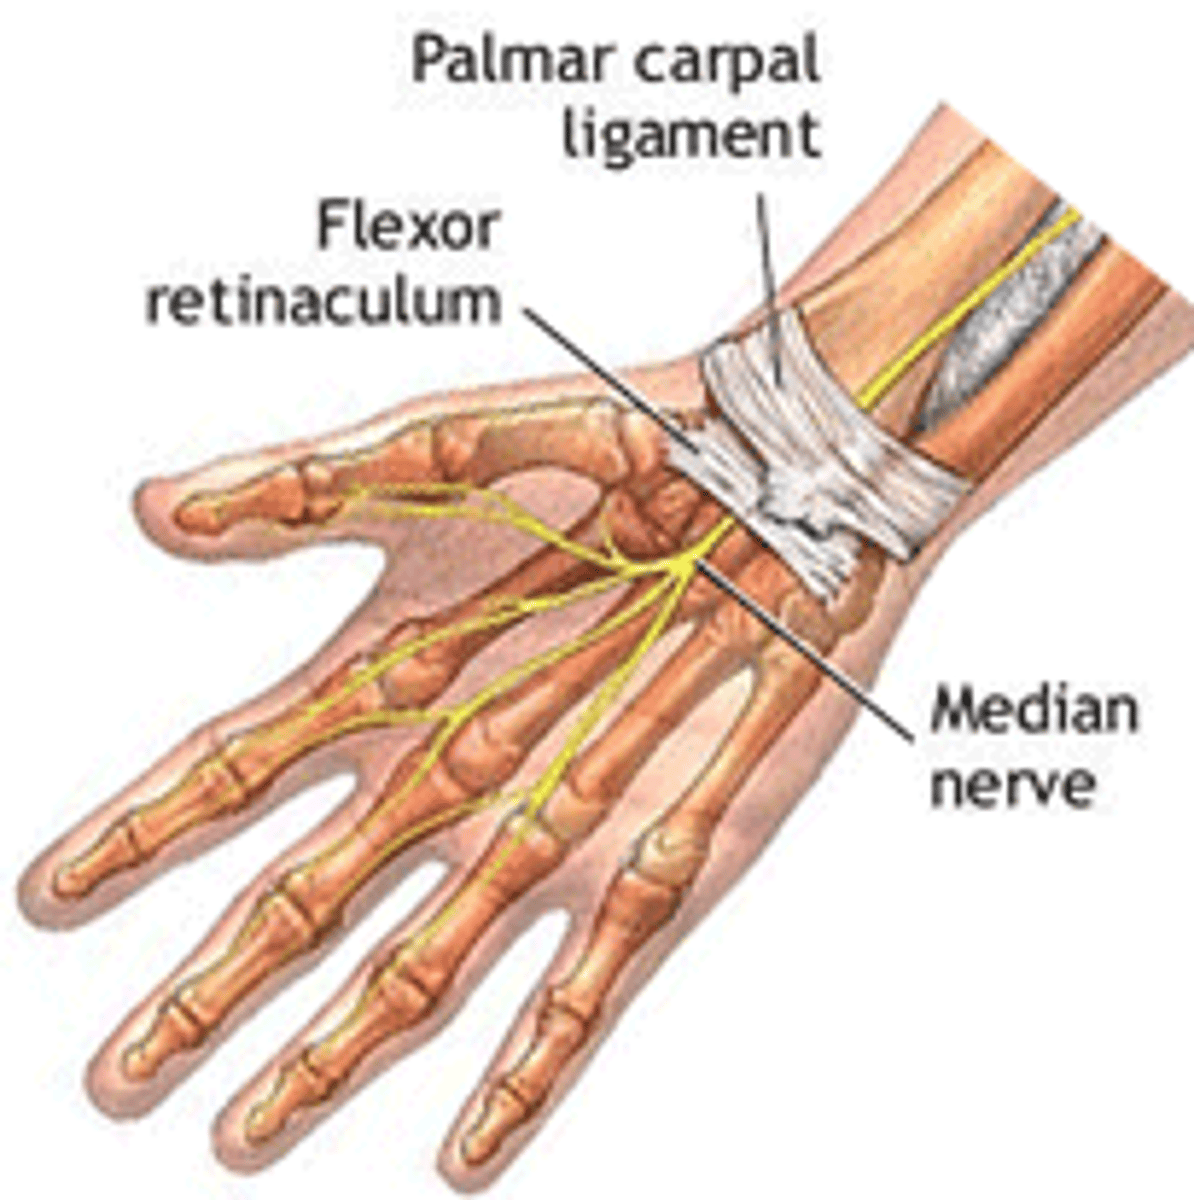

(Antebrachial fascia's Transverse bands:) Flexor retinaculum (transverse carpal ligament)

forms the roof of the carpal tunnel, which contains flexor tendons and the median nerve

(Antebrachial fascia's Transverse bands:) Palmar carpal ligament:

in the anterior region superficial to the flexor retinaculum, and continuous with the extensor retinaculum in the posterior region

Muscles of the forearm Anterior (flexor-pronator) compartment communicates with

central compartment of hand through the carpal tunnel without a fascial barrier

-Passes through the carpal tunnel

-Passes through carpal tunnel